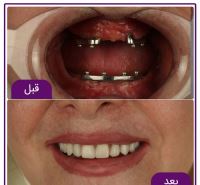

• گالری

ظاهر طبیعی: با نصب دندان مصنوعی فوری بر روی ایمپلنت، بیماران میتوانند به طور فوری از ظاهر طبیعی دندانهای خود بهرهبرده و از خنثی خوردن غذا و لبخند بهرهمند شوند.

برای کاشت ایمپلنت فوری یا ایمپلنت یک روزه، نیازی نیست ابتدا مراحل چند ماهه جوش خوردن ایمپلنت به استخوان را پشت سر بگذارید و پس از آن روکش بر روی دندان تان نصب شود، بلکه در همان روزی که ایمپلنت در دهانتان قرار می گیرد روکش دندان هم بر روی آن نصب می شود. در درمان ایمپلنت به صورت دیجیتال به منظور بررسی استخوان فک و همچنین موقعیت قرار گرفتن رشته های عصبی، از مدل سازی کامپیوتر سه بعدی استفاده می شود. با این شرایط متخصص دندانپزشک با کمترین شکافی به کاشت ایمپلنت دندان می پردازد. به دلیل شکاف کمتر در این روش، درد کمتری برای بیمار وجود خواهد داشت. همچنین به دلیل قرار گرفتن اطلاعاتی بسیار دقیق در دست متخصص دندانپزشک، کمترین میزان آسیب و خطا در این نوع روش درمانی دیجیتال وجود دارد. در کاشت ایمپلنت دیجیتال برای جلوگیری از آسیب عصب و دندان های کناری، یک هدایت کننده (گاید جراحی) بر روی دندان ها نصب می شود. که همین راهنما به برش های دقیق و کوچک تر متخصص دندانپزشک کمک می کند.

در مرحله آخر و در روز جراحی و بلافاصله بعد از قرار دادن ایمپلنت، روکش ایمپلنت که دارای ظاهری بسیار طبیعی و زیبا می باشد، برای بیمار نصب خواهد شد. در واقع در روش ایمپلنت دیجیتال، بیمار حتی یک روز هم بدون دندان نمی ماند.